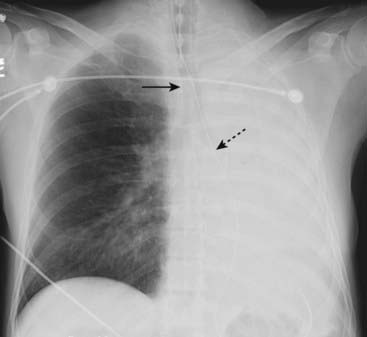

Figure 5-3 Atelectasis of the left lung.

There is complete opacification of the left hemithorax with shift of the trachea (solid black arrow) and the esophagus (marked here by a nasogastric tube, dotted black arrow) toward the side of the atelectasis. The right heart border, which should project about a centimeter to the right of the spine, has been pulled to the left side and is no longer visible. The patient had an obstructing bronchogenic carcinoma in the left main bronchus.